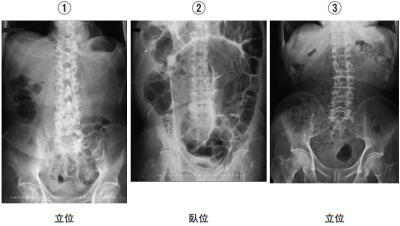

腹部エックス線写真を別に示す。腹部の診察で波動が認められると考えられるのはどれか。

腹部診察で波動を認めるのは腹水貯留時。

④は腹水貯留により腹部の透過性が低下している。